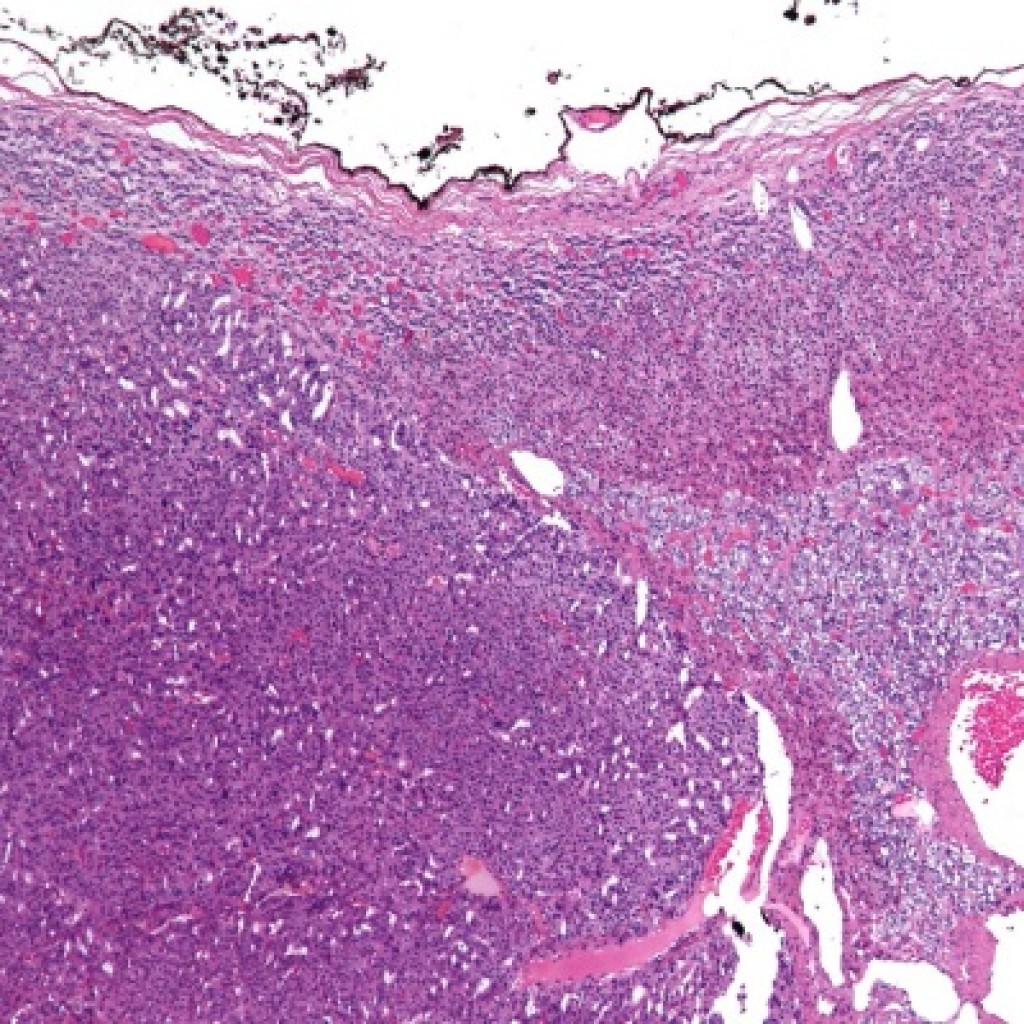

Fonte: Wikimedia Commons